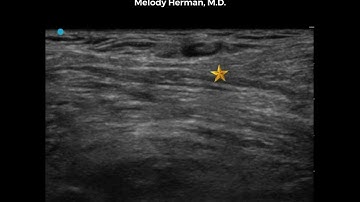

New Scanning Tutorial for Suprainguinal Fascia Iliaca Block